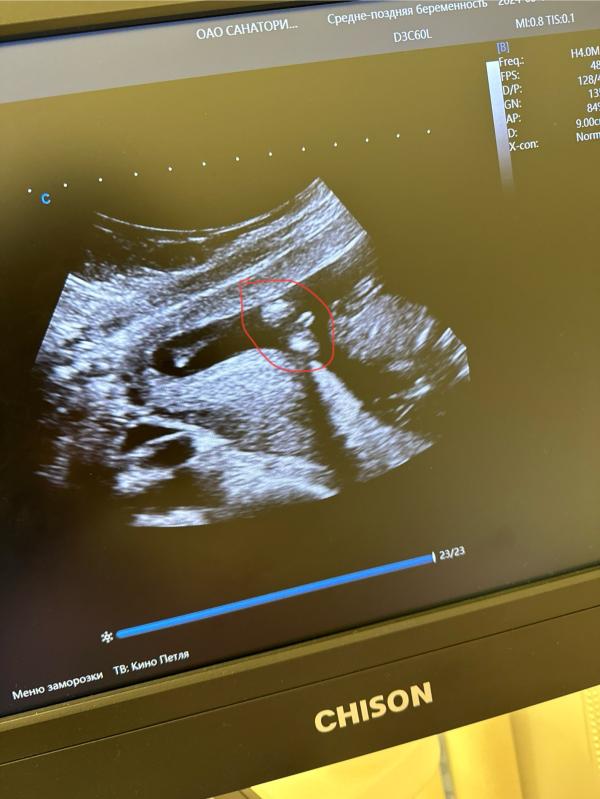

Мальчик правда?

Мальчик, правда?))

Девочка, это на половые губы больше похоже, но это только предположение

На половые губы похоже

Мальчик. У моей между ножек ничего не было

Должен быть пенис виден, тут его не вижу

Но опять же УЗИ это так спорно

Нужно ещё попозже сделать

Спорно

На половые губы тоже похоже